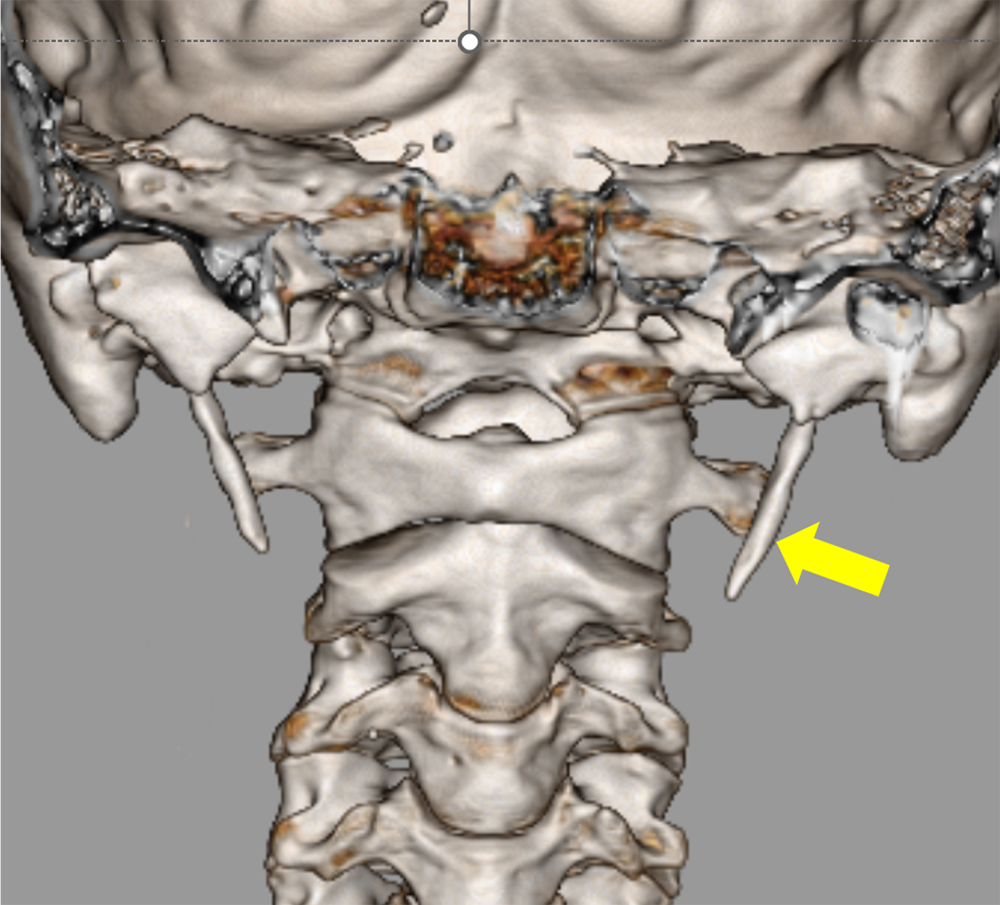

交通外傷後に構音障害が持続し、脳梗塞と診断された患者。内頸動脈解離による閉塞が疑われ、造影CTが施行された。造影CTで左内頸動脈の閉塞を指摘、原因として解離が疑われた。

また、茎状突起の過長はないが、解離部近傍に茎状突起先端が近接しており、茎状突起による内頸動脈解離が疑われたため、茎状突起切除術後に狭窄部ステント留置となった。

過長茎状突起に関連した内頸動脈解離は稀と言われているが、その報告数は近年増加してきている。本症例でも茎状突起に過長はないものの、内頸動脈に近接していた。

DSAでは周囲骨が subtractionされ、頸部エコーや MRA においては茎状突起が描出されないため、茎状突起の評価が十分に行うことができない。そのため、内頸動脈解離急性期での診断の際に、過長茎状突起の有無の評価や内頸動脈と茎状突起の位置を描出するのにCTA が有効であると考えられる。

茎状突起周囲は下顎骨や乳様突起に囲まれており、3D 画像のみでなくCTAの axial view の元画像などで茎状突起と頸動脈が近接していないか確認するのがよいと考えられる。